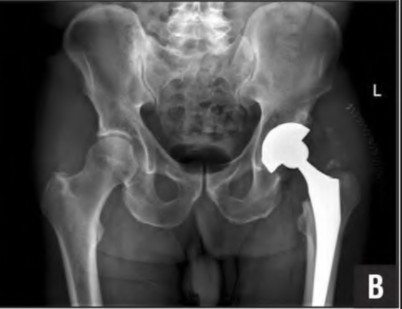

A 72-year-old female falls and sustains a periprosthetic femur fracture around her cementless total hip arthroplasty. Radiographs reveal a fracture extending just distal to the tip of the stem. The stem is radiographically loose, but there is excellent proximal and distal bone stock. According to the Vancouver classification, what is the fracture type and the recommended surgical treatment?

A 75-year-old female sustains a fall 5 years after a cementless THA. Radiographs show a periprosthetic femur fracture occurring around the stem tip. Intraoperative assessment reveals the stem remains firmly fixed in the metaphysis, and the proximal bone stock is adequate. According to the Vancouver classification, what is the fracture type and the standard recommended treatment?